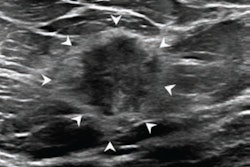

Guldogan and colleagues evaluated the performance of a commercially available AI system (Koios DS Study Tool, version 2.3.0, Koios Medical) for BI-RADS category assessment in breast masses detected on breast ultrasound. The researchers included data from 715 breast masses detected in 530 women. Of the total masses included, 134 were malignant while 581 were benign.

The AI model confirmed that no lesions categorized as BI-RADS 2 were malignant, while two lesions categorized as BI-RADS 3 were confirmed to be malignant. The team reported that by considering BI-RADS 2 lesions as categorized by AI as safe, radiologists could potentially avoid 18 out of 163 of benign lesion biopsies and 110 out of 238 follow-ups.

Furthermore, the algorithm hypothetically downgraded 29.4% (142/483) of the BI-RADS 3, 4, and 5 lesions to BI-RADS 2 or 3. It also upgraded 122 out of 470 benign or possibly benign lesions as suspicious, with a low risk of malignancy.